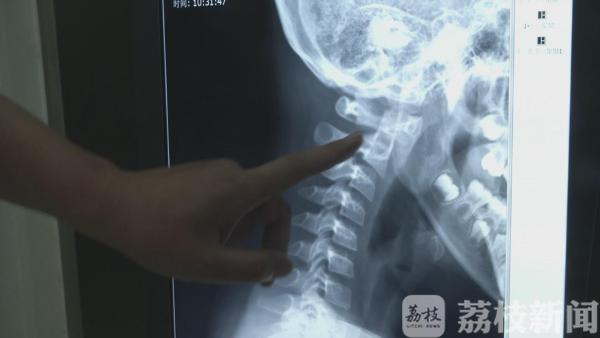

前不久,扬州市妇幼保健院骨伤科接诊了一名年仅八岁的患者。家长介绍,今年以来,小朋友总喊头疼、眩晕。起初家人以为低血糖并没在意,最近情况越发严重才赶来就医。经全面检查,医生诊断,孩子患上了颈椎病,“肇事者”是电子产品。

低龄儿童患病是偶发案例,但颈椎病的年轻化趋势十分明显。30多岁的白领小李正在做颈椎理疗,医院每天也会接诊大量的颈椎病患者。有研究表明,我国20年间颈椎病平均发病年龄下降了16岁。有专家甚至发出预警:颈椎病,正在拖垮年轻一代。究其原因,主要有两点:一是长期的伏案或低头工作、学习;再者,就是电子产品入侵大家的生活。